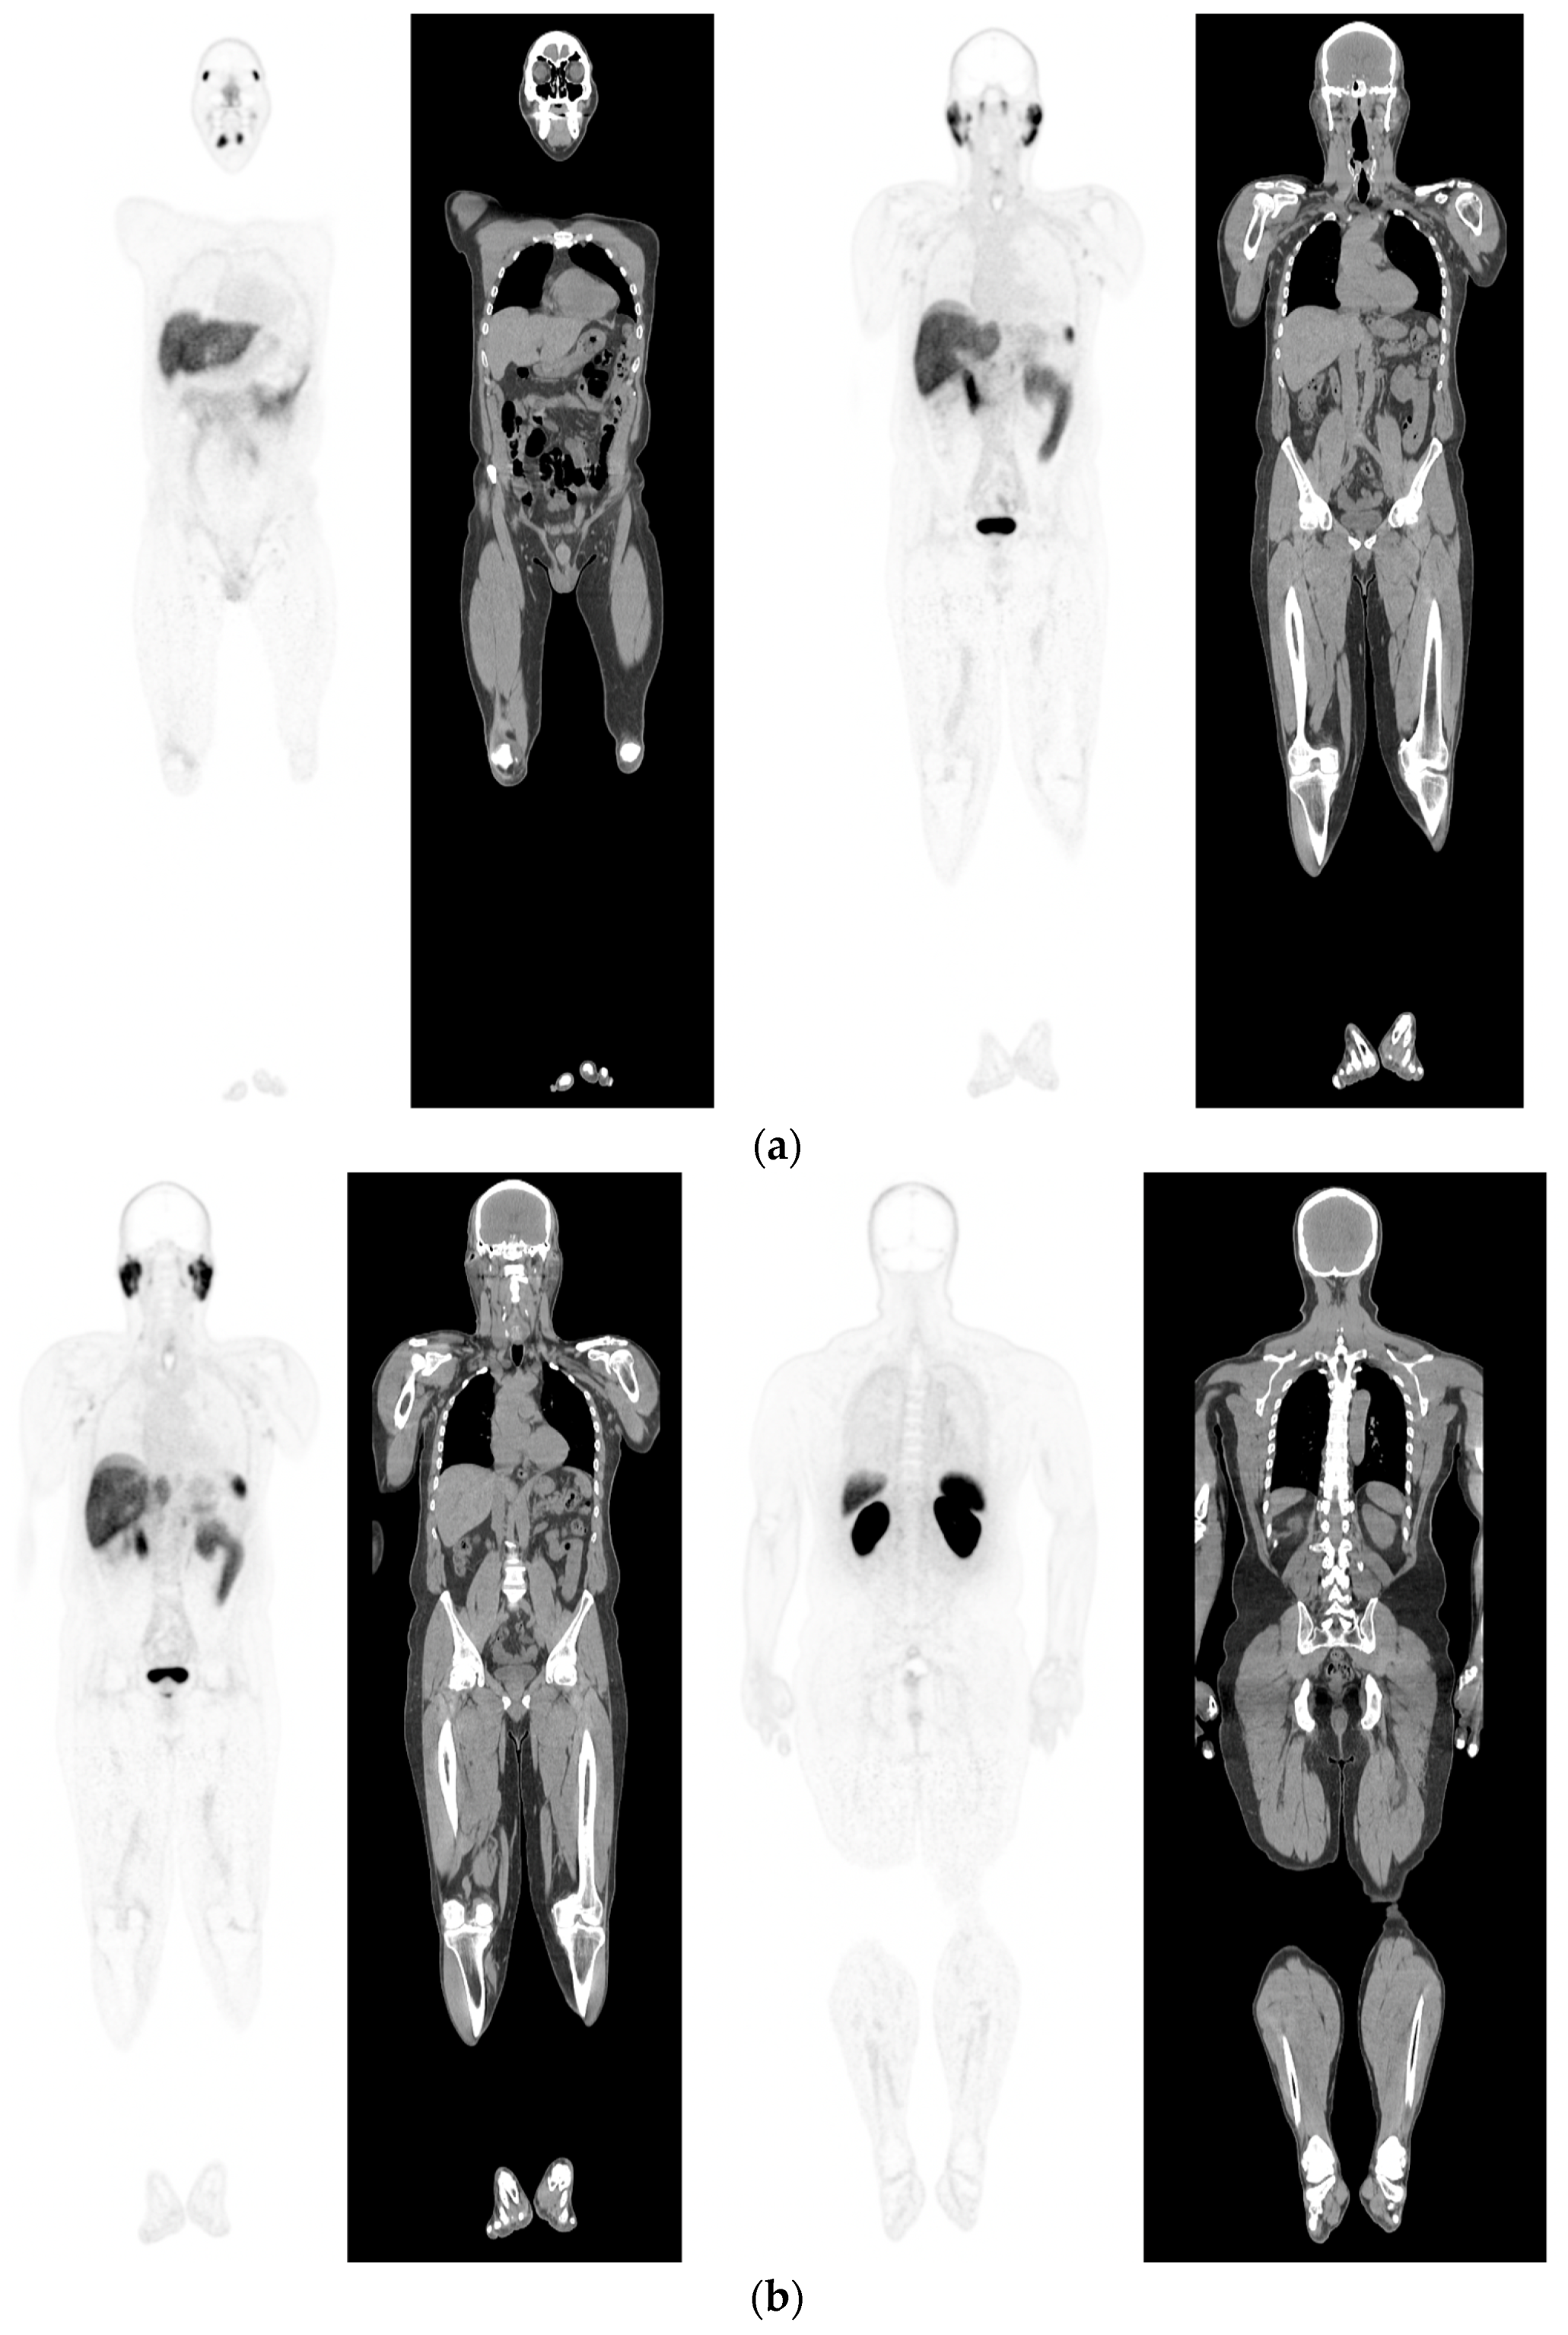

- McEwan, L.M.; Wong, D.; Yaxley, J. Flourodeoxyglucose positron emission tomography scan may be helpful in the case of ductal variant prostate cancer when prostate specific membrane antigen ligand positron emission tomography scan is negative. J. Med. Imaging Radiat. Oncol. 2017, 61, 503–505. [Google Scholar] [CrossRef]